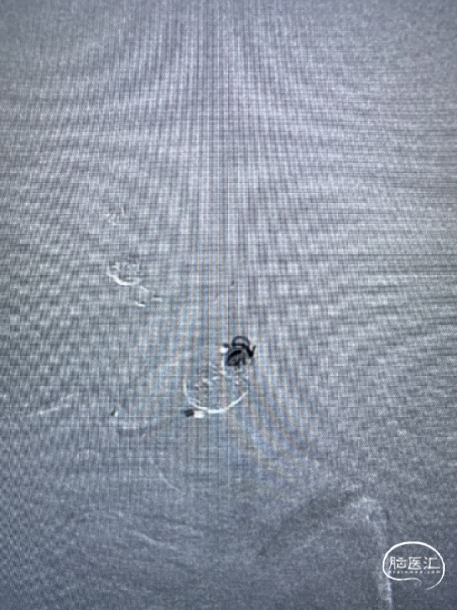

术后正侧位所见